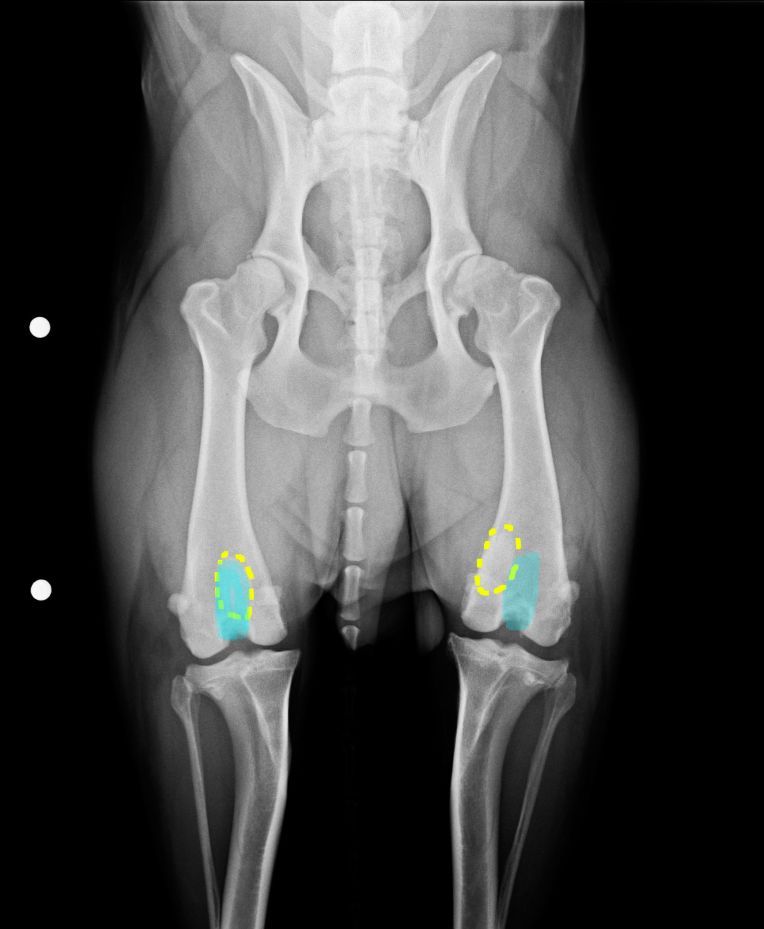

更にERの検査では、左脚の膝蓋骨脱臼を確認。

大腿骨にある膝蓋骨が収まる滑車溝が浅いみたいで、脱臼しやすい骨の状態なんだそうです。

滑車溝が浅いのは恐らく生まれつきのモノで、前十字靭帯断裂も、これを庇っての事だったんじゃないかというのが、ERの見解。

↓ 楕円形に見えるのが膝蓋骨(膝のお皿)

左脚(写真右側)の膝蓋骨が滑車溝のところにない。